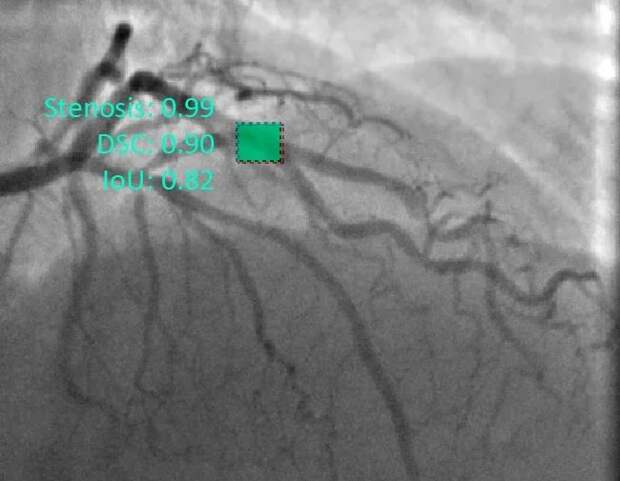

Международный коллектив ученых разработал алгоритм, который находит сужения кровеносных сосудов сердца на диагностических изображениях. В 94 процентах случаев модель верно определяет проблемные участки на картинке в реальном времени. Это поможет кардиологам автоматически выявлять зоны патологических изменений у пациентов с ишемической болезнью сердца во время коронарной ангиографии.

Сравнение параметров нескольких нейросетей показало, что самая точная нейросеть может анализировать по три картинки в секунду с точностью 95 процентов, а самая быстрая обрабатывает по 38 изображений в секунду с точностью 83 процента. Оптимальным вариантом оказалась нейросеть, за секунду анализирующая по десять снимков с точностью 94 процента. В зависимости от нужд оператора можно использовать как более быстрые, так и более точные модели.

"Данные исследования, помимо обнаружения стенозов, могут быть использованы для автоматизированной оценки степени поражений и гемодинамики артерий сердца. Архитектура нейросети и использованные методы машинного обучения позволили добиться 95-процентной точности при работе в реальном времени. В дальнейшем мы планируем разработать программу, чтобы направлять действия хирургов во время имплантации биопротеза клапана аорты", — поделился Евгений Овчаренко, кандидат технических наук, руководитель проекта по гранту РНФ, заведующий лабораторией новых биоматериалов Научно-исследовательского института комплексных проблем сердечно-сосудистых заболеваний (Кемерово).